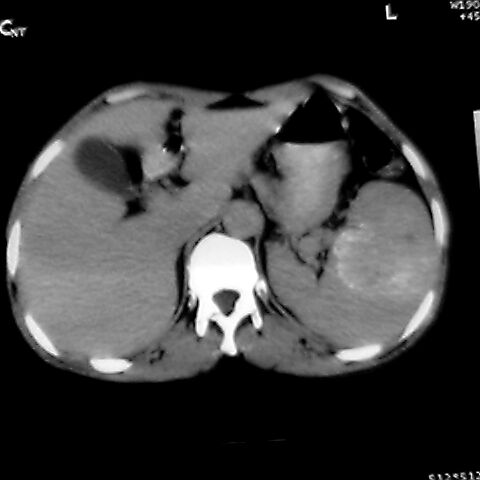

女 48岁 食道癌术前体检发现脾占位。

脾胀内部巨大低密度肿块,边界清或不清,中心坏死,轻度增强,内见散在钙化,结合食道癌病史多考虑:转移癌.

1肝右下叶小囊肿2右肾上极囊肿或错构瘤3脾脏不典型血管瘤可能性大.

脾脏低密度灶伴钙化,增强化明显,中心见液化坏死灶,强化延时明显。考虑血管瘤。转移瘤待排。

右肾见类圆形低密度影.结合病史.脾及右肾转移性ca可能性大

1,脾血管瘤。2,右肝,右肾小囊肿。